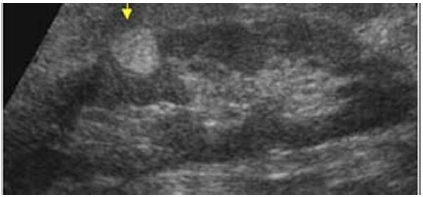

Paciente assintomático, com o seguinte achado na ultrassonografia de abdome. Qual a principal hipótese diagnóstica?